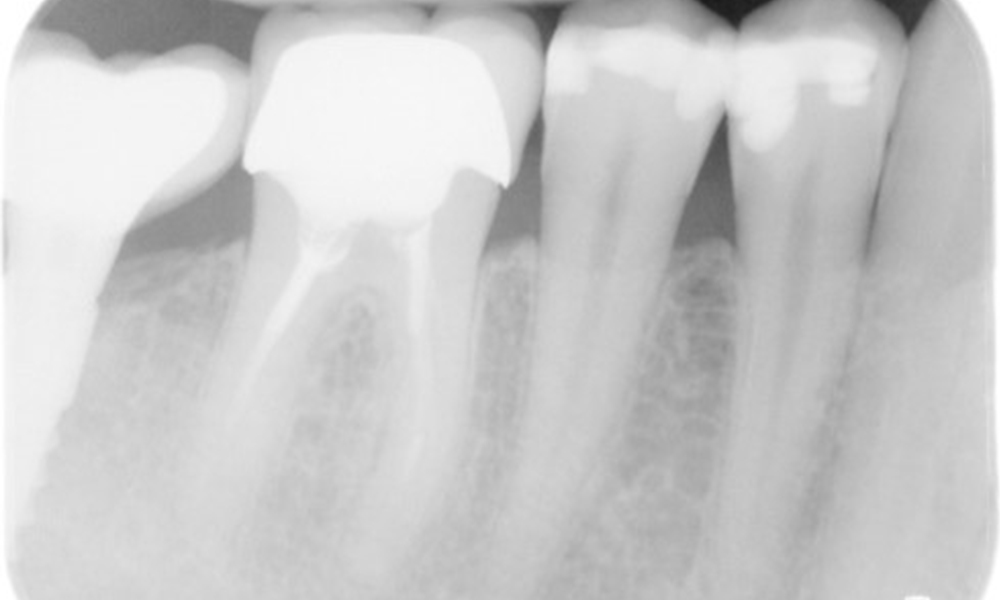

Zahnfilme (bzw. Bissflügelröntgen)

Zahnfilme (bzw. Bissflügelröntgen) aufgenommen am: 18.02.2021

Röntgenaufnahme zeigt Knochenabbau

Die Röntgenaufnahme zeigt den Knochenabbau.